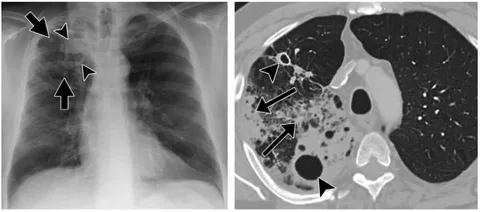

Toraks BT taraması, bilgisayarlı tomografi (BT) teknolojisinin kullanıldığı bir tıbbi inceleme yöntemidir. Bu tarama, göğüs bölgesinin iç yapısını ve organlarını üç boyutlu görüntülerle gözlemlemek için kullanılır. Toraks BT taraması, akciğerlerin, kalbin, damarların, göğüs kemiğinin ve diğer yapıların detaylı incelemesini sağlar.

Toraks BT taraması, akciğer hastalıklarının tanısında ve izlenmesinde yaygın olarak kullanılır. Akciğer kanseri, akciğer iltihapları, akciğer embolisi gibi durumlar bu tarama ile değerlendirilir.

Toraks BT taraması sonuçları, bir radyolog tarafından incelenir ve bir rapor halinde sunulur. Bu sonuçlar, hastanın doktoru tarafından değerlendirilir. Sonuçlar, göğüs bölgesindeki herhangi bir anormalliği, tümörü, damar tıkanıklığını veya diğer sorunları gösterebilir.